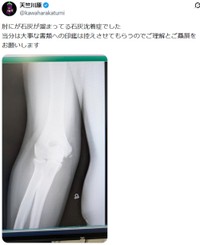

9日に「しょーもない動きをして両肘痛めたせいで大事な書類の印鑑が押せない」と記していたが、この日の投稿で、肘の関節付近に小さな白い影の見えるエックス線写真とともに「肘にが石灰が溜まってる石灰沈着症でした」と説明。石灰沈着症は体内の組織にリン酸カルシウムの結晶が沈着し、炎症や痛みを引き起こす病気で、肩関節の腱板に発生することが多いとされている。